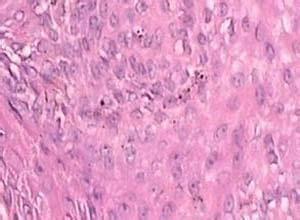

简介单发性毛鞘瘤(solitary trichilemmoma)1962年由Headington和Prench首先报告,为颜面部特别是鼻和颊部发生的单发性小丘疹,直径3~8mm,无特征性临床形态。